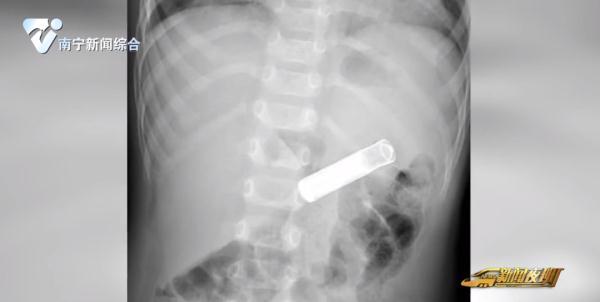

8月25日晚,南寧一名家長帶著自己1歲11個月大的兒子來到南寧市第二人民醫院兒科急診,焦急地表示孩子在玩耍時吞下了一顆7號電池。醫院消化內科醫生接到緊急會診通知后,立即趕往兒科急診。CT報告顯示:孩子胃內確實存在長度約4cm的長條狀異物。

考慮到情況緊急,醫生與患兒家屬溝通病情后,決定采取內鏡下胃內異物取出術。在進行麻醉后,醫生通過胃鏡配合圈套器,將一枚7號電池取出。